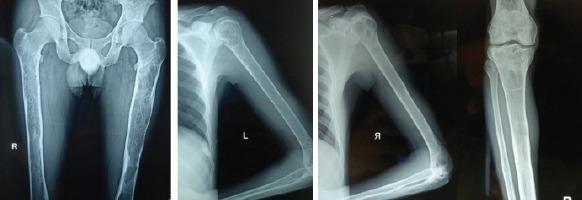

A 38-year-old man presented to our outpatient department with a solitary, painless soft-tissue swelling of the left proximal tibia noticed 6 months back, which has gradually progressed to a present size of 9x5 cm over a period of 6 months. General physical examination revealed moderate splenomegaly. Radiographs showed an osteolytic lesion in the left proximal tibia without cortical erosion. Radiographs for skeletal survey revealed similar osteolytic lesions elsewhere. Hematological investigations revealed thrombocytopenia. A serum protein electrophoresis was found to be normal and the urine was negative for myeloma proteins. Blood workup for endocrine abnormalities was within normal limits. MRI of the lesion suggests bone infarct. Biopsy from the lesion showed a giant binucleate storage cell filled with glucocerebrosides suggestive of Gaucher's disease. The diagnosis was confirmed by elevated plasma levels of glucocerebrosidases.

一名38岁男性因6个月前发现左胫骨近端有一个孤立的、无痛性软组织肿胀前来我院门诊就诊,在6个月内逐渐发展至目前9×5厘米大小。全身体格检查发现中度脾肿大。X线片显示左胫骨近端有一个溶骨性病变,无皮质侵蚀。骨骼检查的X线片显示其他部位也有类似的溶骨性病变。血液学检查发现血小板减少。血清蛋白电泳正常,尿液中骨髓瘤蛋白检测为阴性。内分泌异常的血液检查结果在正常范围内。病变的磁共振成像提示骨梗死。病变活检显示一个充满葡萄糖脑苷脂的巨大双核贮积细胞,提示戈谢病。血浆葡萄糖脑苷脂酶水平升高证实了诊断。